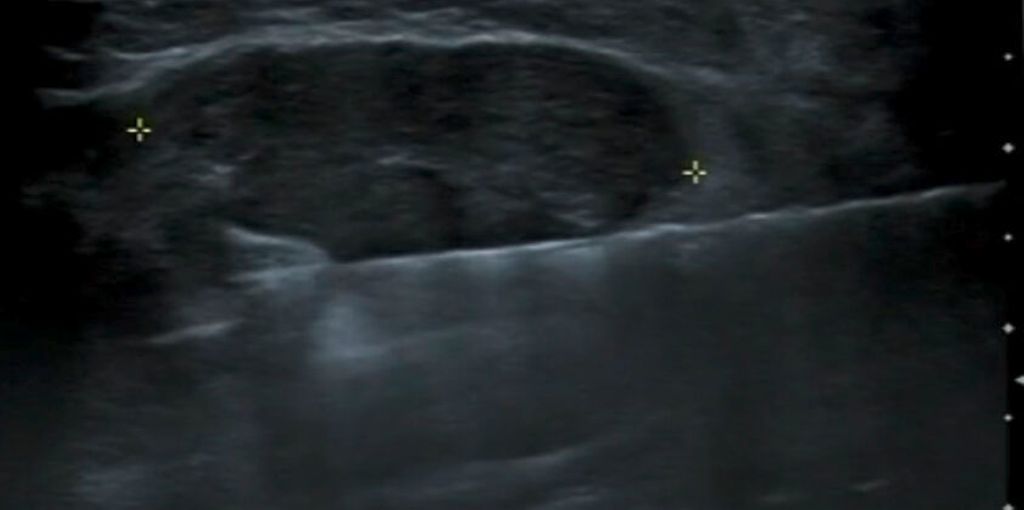

Abb. 2: Einführen der Nadel in flachem Winkel parallel zum Ultraschallkopf

Die US-VAB wird üblicherweise in lokaler Anästhesie durchgeführt. Ein ruhiges und umsichtiges Vorgehen, achtsame Patientinnenführung sowie eine störungsfreie Umgebung reduzieren das Stressempfinden bei der Patientin und minimieren Komplikationen.11 Die Lagerung auf einer Untersuchungsliege soll für die Patientin bequem sein, sodass sie die Position für die Dauer der VAB halten kann, und muss so gewählt werden, dass ein idealer Zugangsweg zur Zielläsion gewährleistet ist. Dies führt auch dazu, dass möglichst wenig umliegendes, gesundes Gewebe verletzt wird (kurzer Zugangsweg). Bei thoraxwandnahen Befunden sollte der Zugang in flachem Winkel erfolgen (Abb. 2). Die lokale Anästhesie (z.B. mit 10–20ml Lidocain 1%) erfolgt durch Quaddelung der Haut und lokale Betäubung in Richtung der geplanten VAB-Nadelführung sowie in der Umgebung der zu entfernenden Läsion. Die Distanz der Läsion zur Haut oder zur Thoraxwand kann dabei durch «Kissenbildung» mit Lokalanästhetikum vergrössert werden. Ein steriles Vorgehen während der gesamten Intervention ist selbstverständlich.